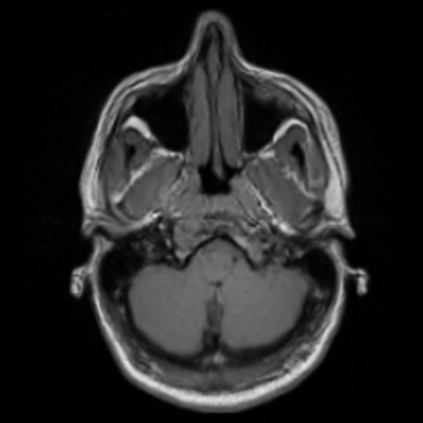

Motion artifacts are a primary source of magnetic resonance (MR) image quality deterioration with strong repercussions on diagnostic performance. Currently, MR motion correction is carried out either prospectively, with the help of motion tracking systems, or retrospectively by mainly utilizing computationally expensive iterative algorithms. In this paper, we utilize a novel adversarial framework, titled MedGAN, for the joint retrospective correction of rigid and non-rigid motion artifacts in different body regions and without the need for a reference image. MedGAN utilizes a unique combination of non-adversarial losses and a novel generator architecture to capture the textures and fine-detailed structures of the desired artifacts-free MR images. Quantitative and qualitative comparisons with other adversarial techniques have illustrated the proposed model's superior performance.

翻译:移动文物是磁共振(MR)图像质量恶化的一个主要来源,对诊断性能产生强烈影响。目前,MR运动的校正要么是预期性的,借助运动跟踪系统,要么是追溯性的,主要是利用成本昂贵的计算迭代算法。在本文中,我们使用名为MedGAN的新颖的对抗性框架,联合追溯性地校正不同身体区域的硬性和非硬性运动文物,而不需要参考图像。 MedGAN利用非对抗性损失和新型生成器结构的独特组合来捕捉无MR图象的纹理和精细详细结构。 与其他对抗性技术的定量和定性比较展示了拟议模型的优异性表现。